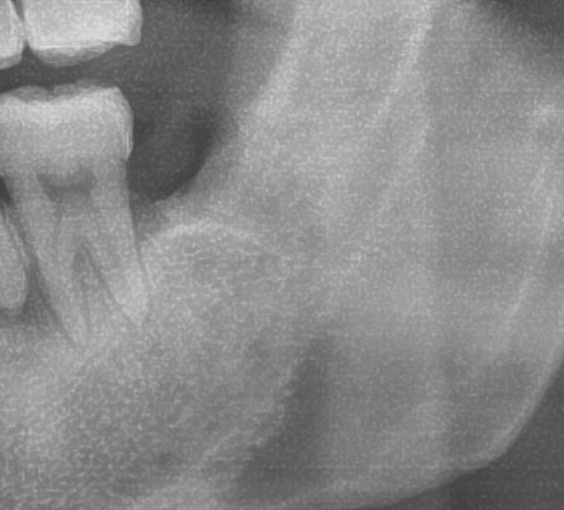

次にパノラマ写真を撮影してみると、左下の親知らずは歯茎の中で手前の歯を押すように斜めに生えているのが確認できました。

親知らずが生えている位置が、神経に近い、あるいは神経に当たっている場合は、大きな病院に紹介する場合もあります。

親知らずの根っこは下歯槽神経からは十分距離があるようです。